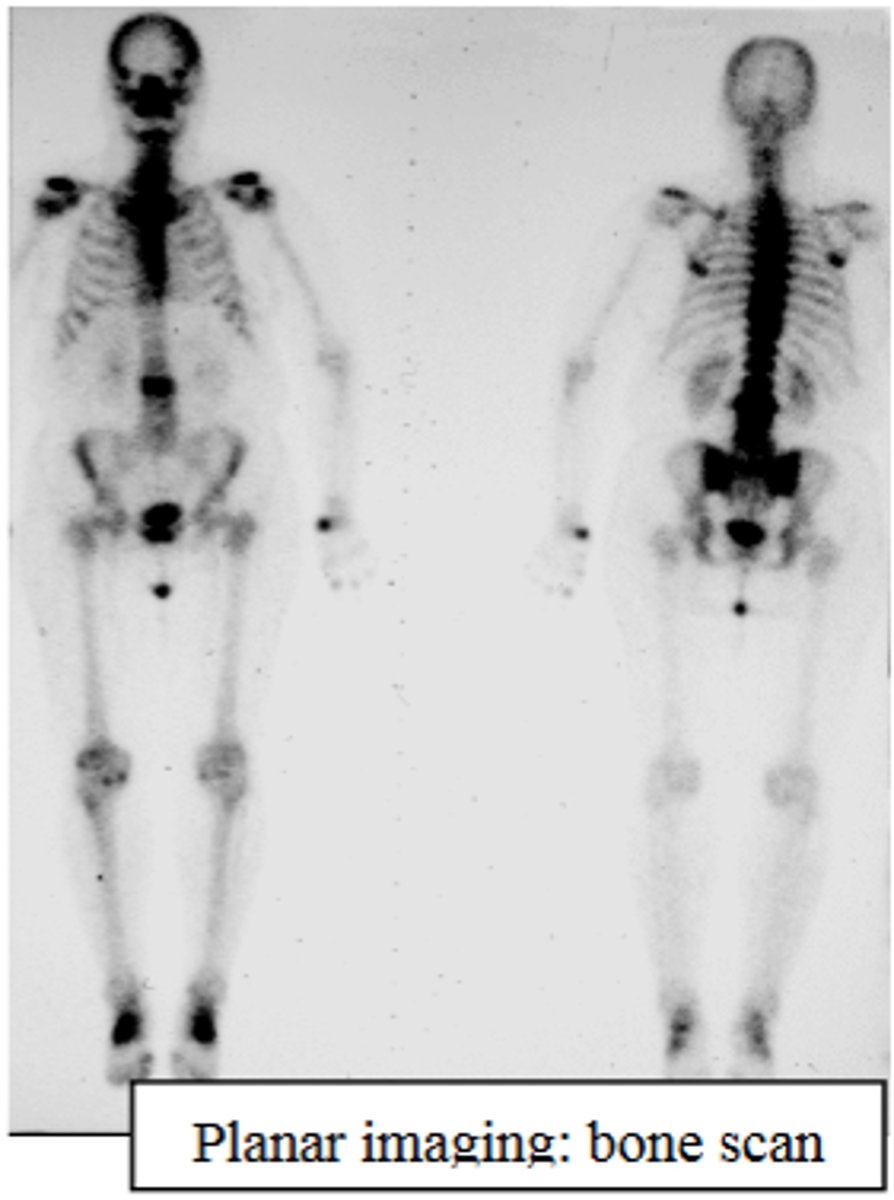

What is planar imaging?

Using a single gamma camera to absorb gamma rays from an area of interest and produce a two-dimensional image.

What is a common application of planar imaging?

Bone scan.